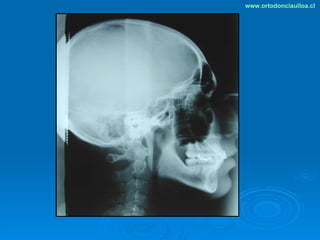

Este documento presenta dos casos clínicos de pacientes que recibieron tratamiento de ortodoncia. El primer caso fue de una paciente femenina de 14 años con apiñamiento dental y mordida cruzada que fue tratada mediante extracción de premolares y alineamiento dental. El segundo caso fue de un paciente masculino de 14 años con clase II esqueletal y desarmonía dentomaxilar que fue tratado con extracción de premolares y corrección de mordida. Ambos casos mostraron mejoría después de 3 años de tratamiento.